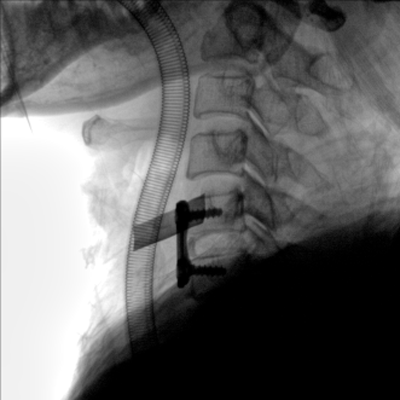

大尺寸動(dòng)態(tài)平板探測(cè)器,高DQE、低噪聲、圖像清晰。采用多分辨率圖像增強(qiáng)處理技術(shù),不同部位不同圖像處理算法,滿足客戶多樣化的需求。

采用智能變頻脈沖透視技術(shù),優(yōu)化圖像質(zhì)量的同時(shí)降低輻射劑量,呵護(hù)醫(yī)患健康